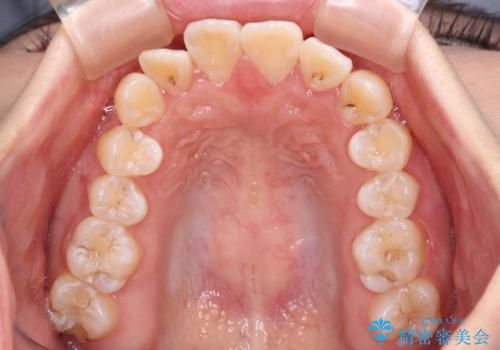

- 前歯のデコボコと八重歯を気にして来院された患者様です。

インビザラインでの治療を希望されていましたが、前歯のクロスバイトや下顎小臼歯の捻転が認められたため、インビザライン単独で治療を行うよりも、ワイヤー装置を併用した方が、治療期間の短縮やトラブル回避できると判断し、ワイヤー装置を併用することとしました。

まずはワイヤー装置により前歯のクロスバイトと下顎小臼歯の捻転を改善し、その後インビザラインにより全体を整える矯正治療を行うこととしました。

前歯のクロスバイトは、インビザラインでの改善中に前歯に過剰な力がかかり、歯髄壊死や歯肉退縮を引き起こすことがあります。また下顎小臼歯は寸胴型のため、捻転を排除することが難しいことが知られています。

それをワイヤー装置にて速やかに改善することで、トータルでの治療期間を短くすることができます。